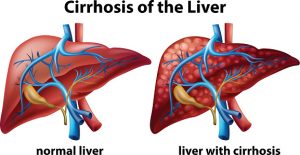

Individuals with chronic liver disease often develop fibrosis – scarring of the liver – which can lead to cirrhosis – a severe form of liver disease that can be deadly. Ascites is a complication of cirrhosis, which can lead to the abdomen swelling and bulging. The peritoneum covers abdominal organs, including the liver, which is probably why the two are associated.

Individuals with chronic liver disease often develop fibrosis – scarring of the liver – which can lead to cirrhosis – a severe form of liver disease that can be deadly. Ascites is a complication of cirrhosis, which can lead to the abdomen swelling and bulging. The peritoneum covers abdominal organs, including the liver, which is probably why the two are associated.